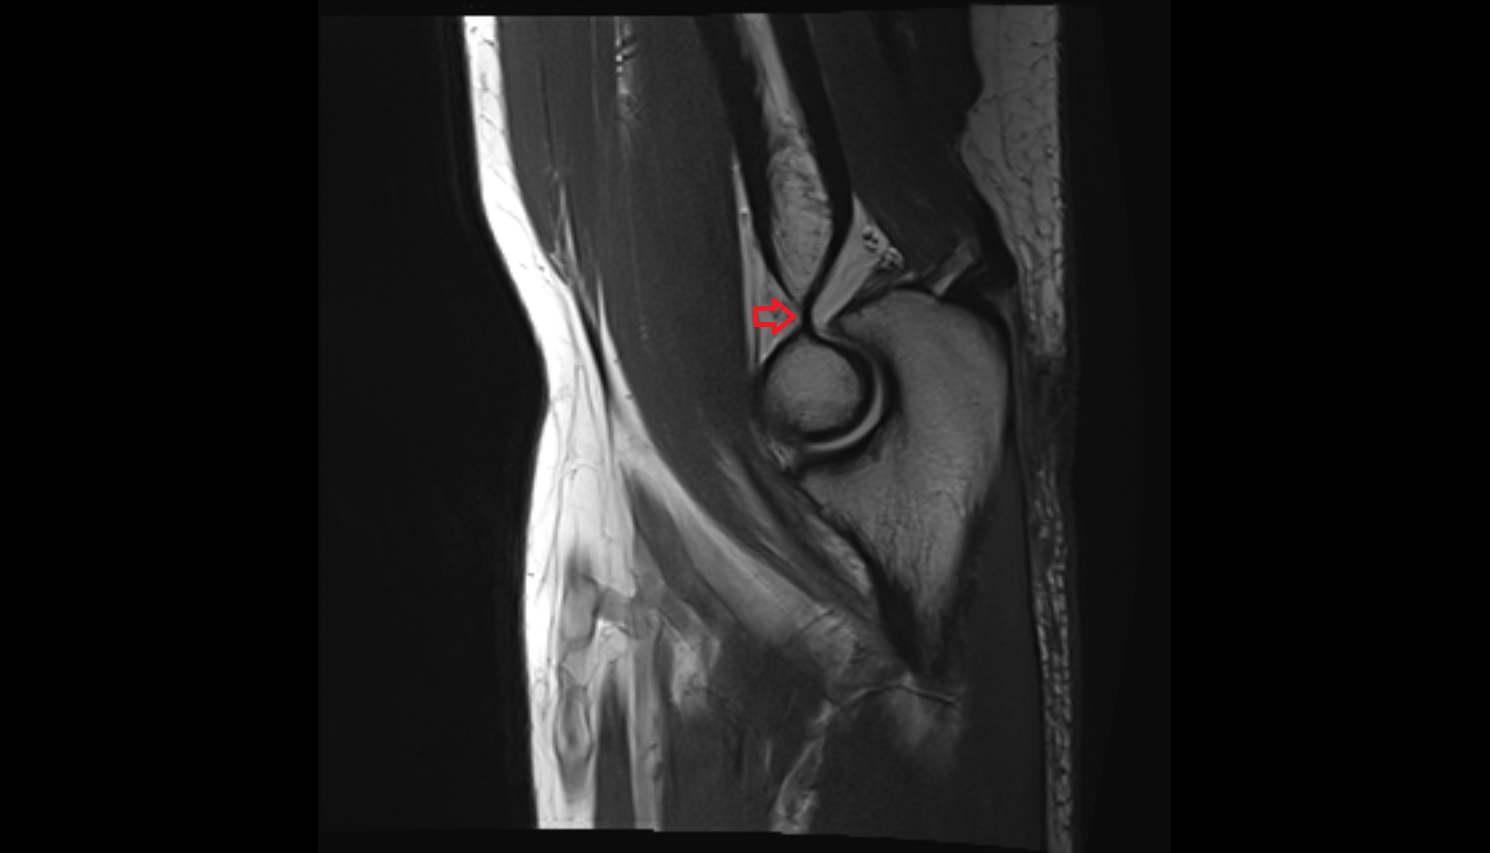

- Anterior cruciate ligament

- Posterior cruciate ligament

- Knee Joint